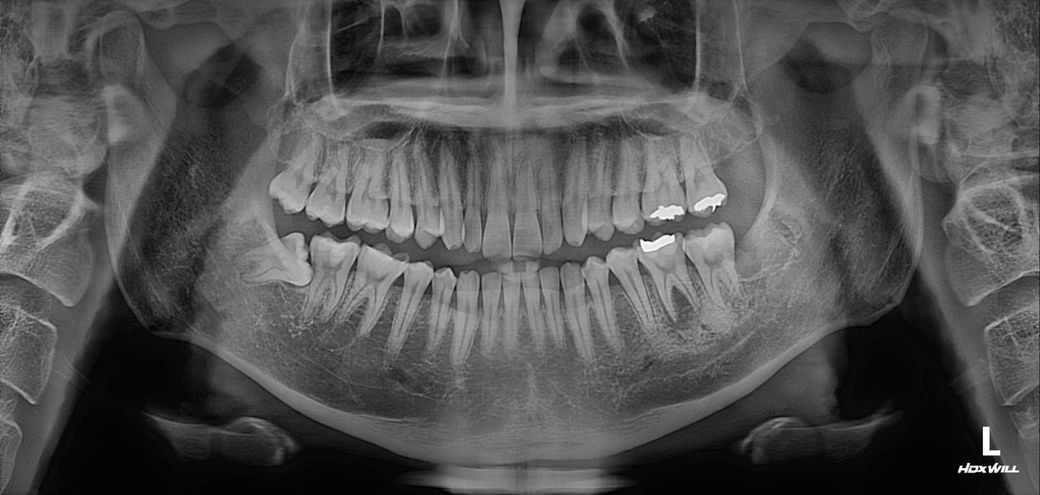

첫번째 사진은 신경치료 받기 전 사진이고 두번째 사진은 신경치료를 받은 후의 사진입니다.

Q2. 치아 뿌리에 금이 가더라도 파노라마 사진에서 염증의 크기가 줄어들까요? 첫번째 사진과 두번째 사진을 비교해봤을 때, 언뜻 보기에 염증크기가 줄어든 거 같아서 여쭤봅니다.

• 1번 째 사진